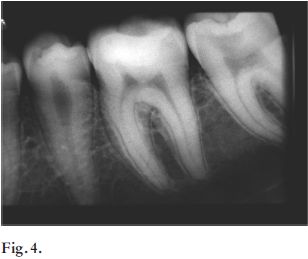

Concomitantemente, Pitts (1) en 1990 afirmó la dificultad que existe de identificar lesiones de caries que involucran tejido dentinario, por el método de inspección visual. Por eso el autor aconseja el uso de radiografías interproximales como complemento en el diagnóstico en la determinación de lesiones que comprometen la dentina, justamente cuando se requiere de tratamientos invasivos (Figs.3, 4 y 5).

Figs. 3, 4 y 5. Se aprecia una lesión cariosa aparentemente incipiente en la pieza 37. En la radiografia se visualiza gran afectación dentinaria, que se correlaciona con la clínica una vez realizada la apertura.